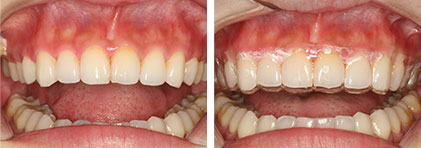

美顏矯正

齒列的改變會影響到臉型的變化,最明顯的就是暴牙造成的嘴唇無法自然閉合,嚴重的影響到整體的美觀。不過大家不知道的部分就是,本院葉醫師最引以為傲的矯正技術,不僅可以把患者的牙齒排列整齊,還可以讓矯正在沒有做整型手術的前提下,進一步的達到微整型或打肉毒的效果。

變臉矯正

這是屬於前後差異最明顯的矯正,最具代表性的是嚴重戽斗的患者,有時為了讓治療的效果更好,除了配戴矯正器、面弓等矯正器具之外,可能還要進一步搭配口腔外科的正顎手術治療。本院會為這類的患者做一個完整的分析,再提出最適合的治療計畫,令整個矯正療程能在患者全盤清楚,完全配合情況下順利完成。